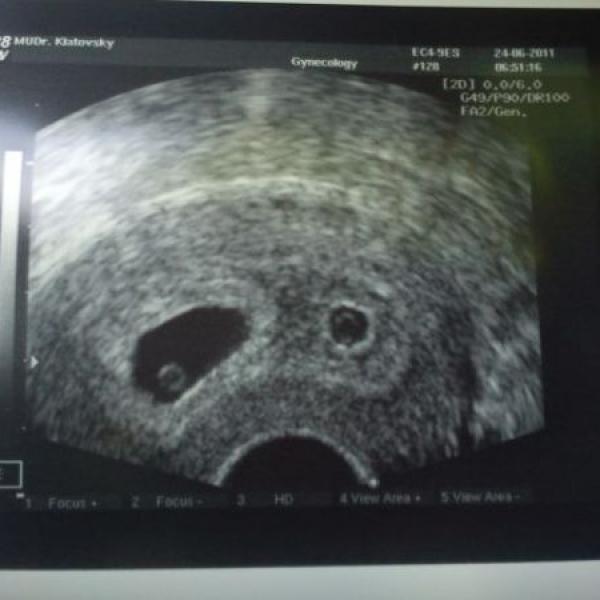

Ewicka88 28.06.2011 Detail ahojky maminky,těhulky a všichni ostatní.Rozhodla jsem se že Vám po včerejší zkušenosti napíšu moje pocity:Začalo to asi takhle jsem nyní těhotná 6+5.Čekám dvojčátka teda spíše č Komentáře jsou momentálně nedostupné. Děkujeme za pochopení. Ewicka88 22.06.2011 Detail Ahojky všechny Vás tu zdravím tady budoucí maminka:-) Jsem v 6TT.:-) Komentáře jsou momentálně nedostupné. Děkujeme za pochopení.